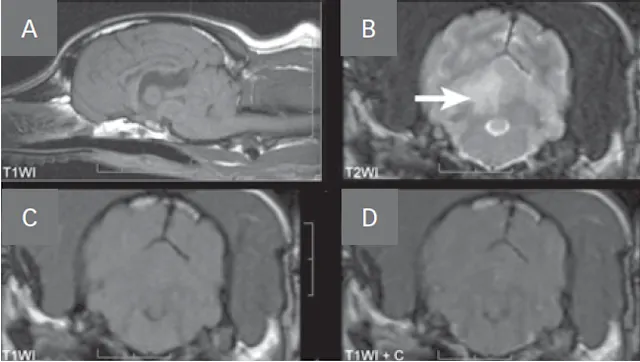

• The MRI appearance of hemorrhagic infarction (Figure 3, see image gallery below) varies greatly as blood cells and hemoglobin degrade (Table 2).

• Hemorrhagic infarcts can be difficult to distinguish from hemorrhagic brain tumors (eg, glioma, hemangiosarcoma).

• The T2*-gradient echo (T2*GRE) sequence is best for identifying hemorrhage as it is hypointense on this sequence.

• T2*GRE is also hypointense for mineralization, air, iron, melanin, and foreign bodies.